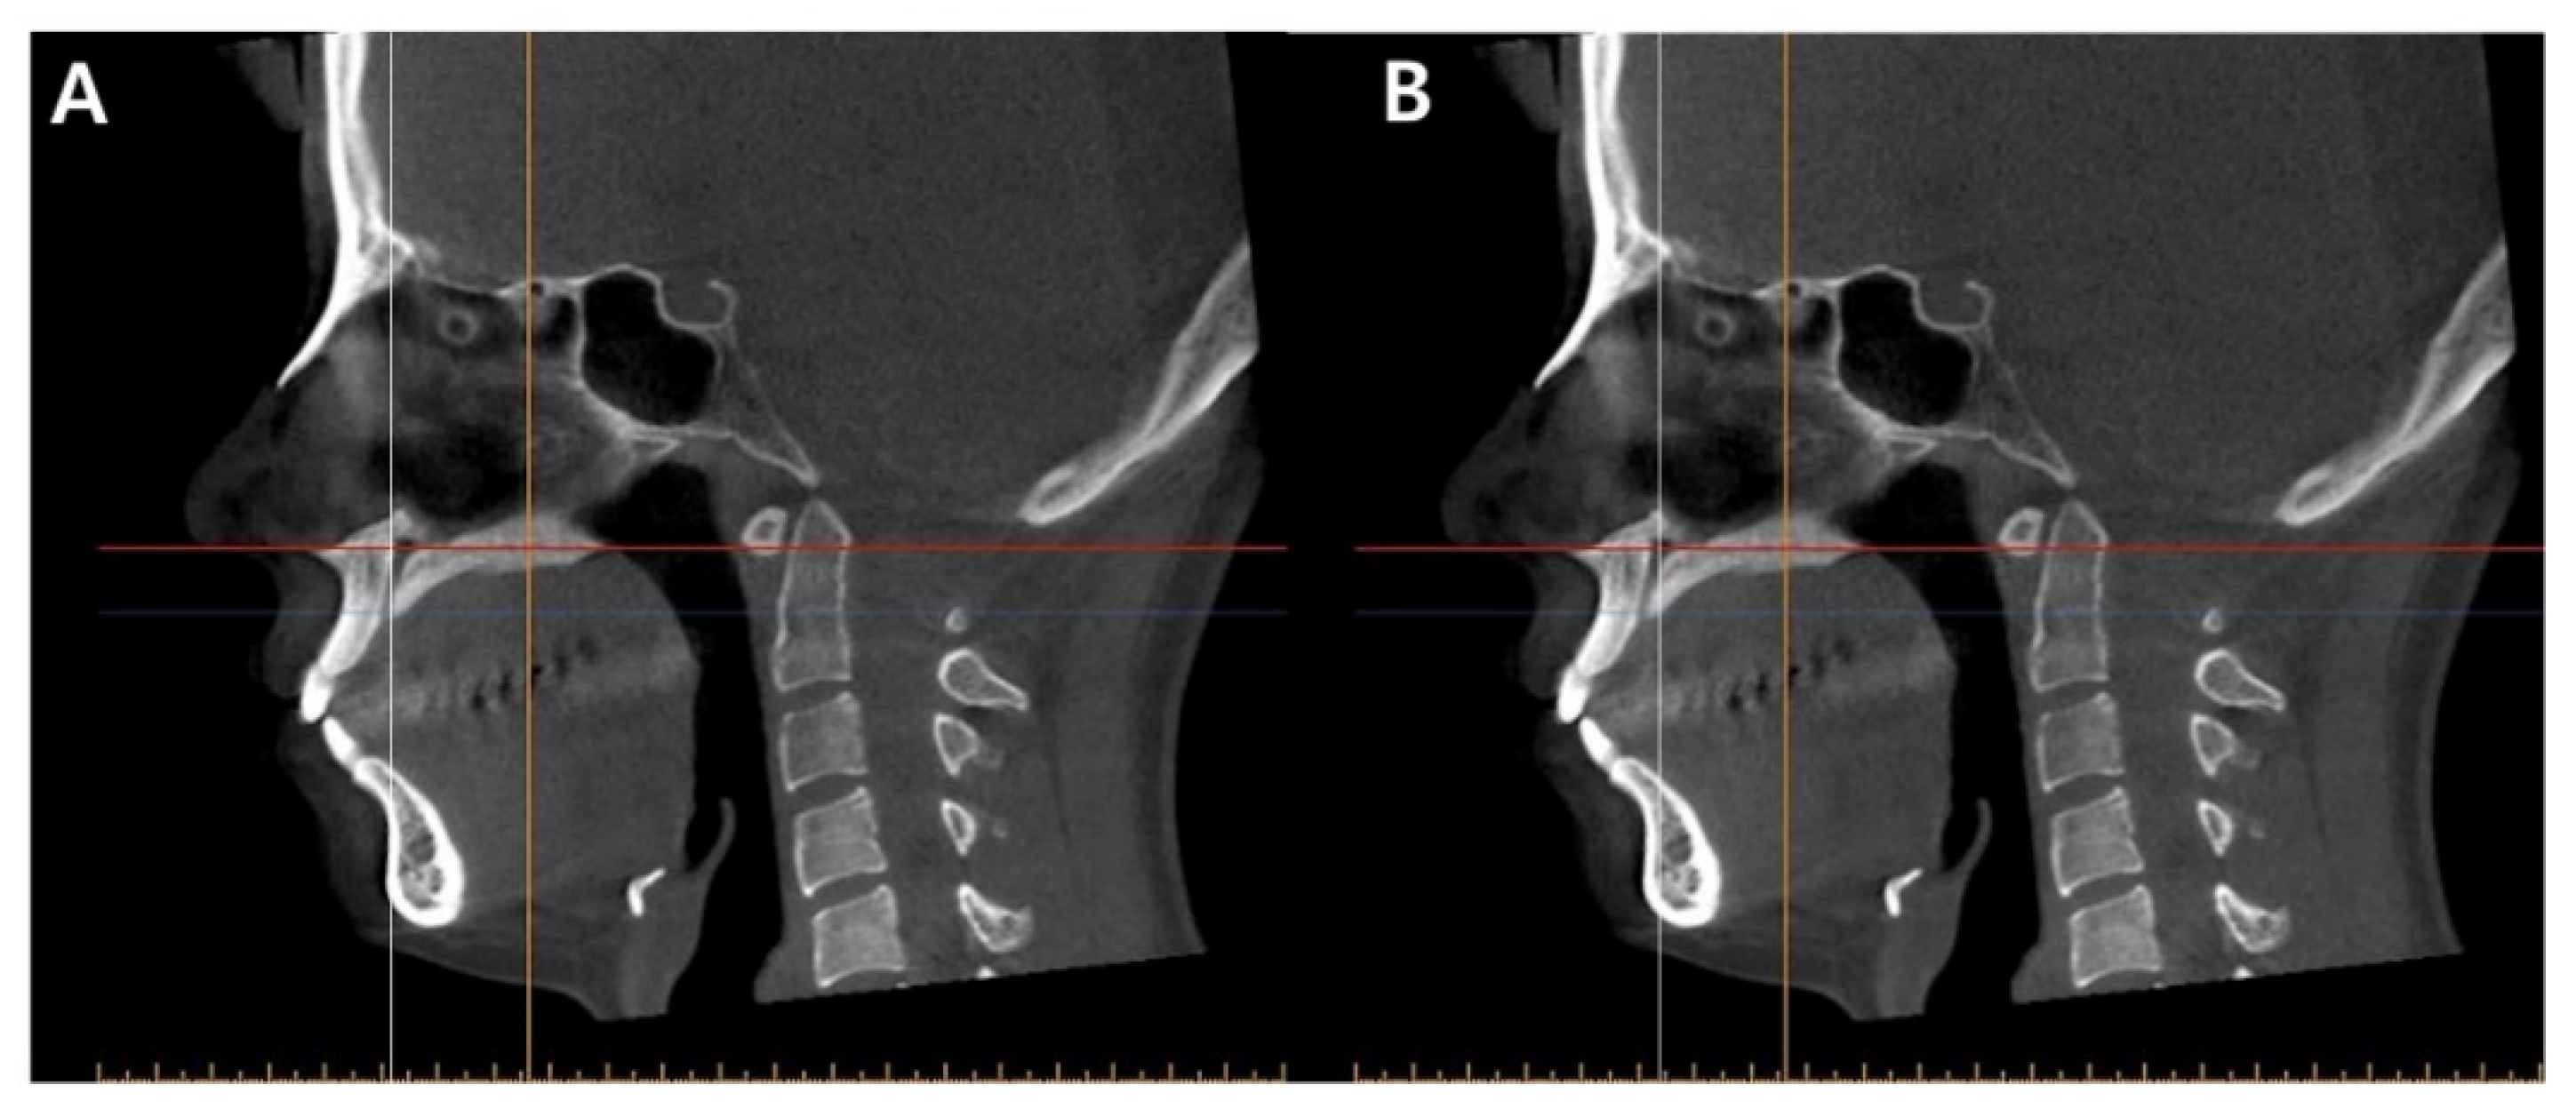

A CBCT Evaluation of Midpalatal Bone Density in Various Skeletal Patterns